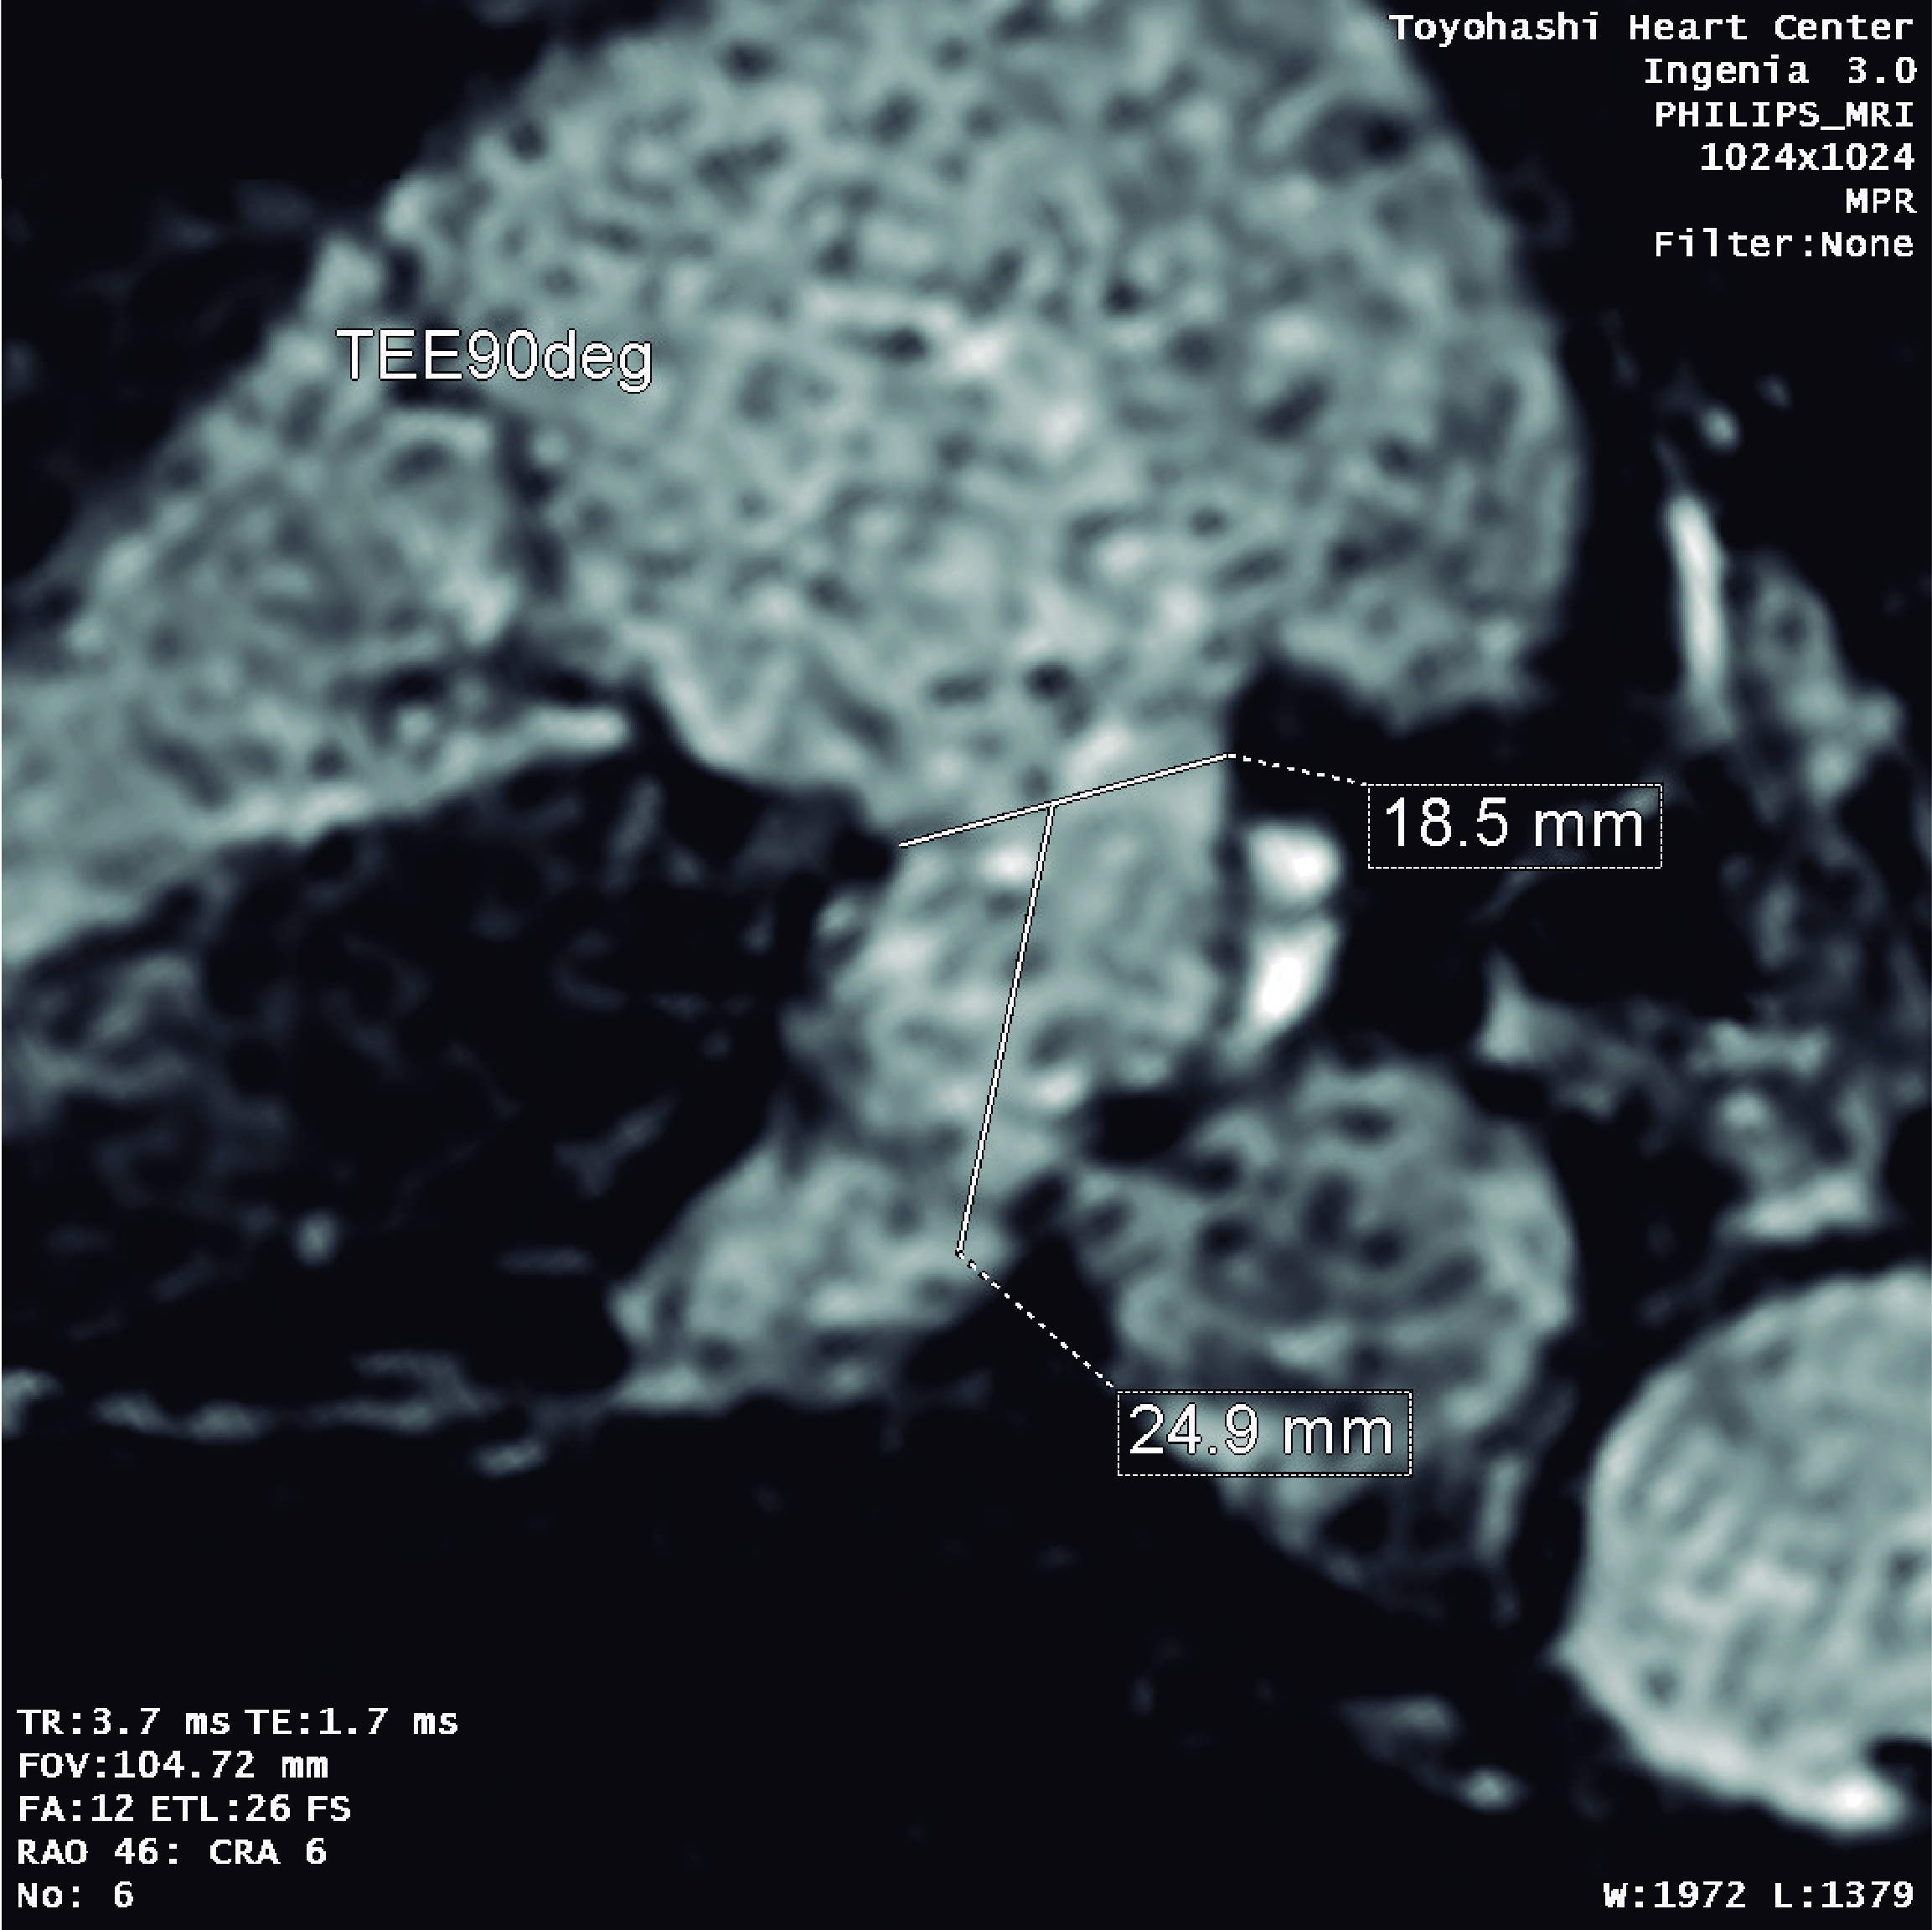

【症例】

80歳代 男性

糖尿病, 高血圧症, 脂質異常症, 持続性心房細動, 食道癌, 胃癌(2020/2), 大腸癌術後(2001,2009), 慢性腎臓病, 高度貧血, TAVI(2019/12 Sapien3 26mm), 冠動脈バイバス術後(2018/04), ラクナ梗塞

しかし出血リスク高く、今回左心耳閉鎖治療予定となる